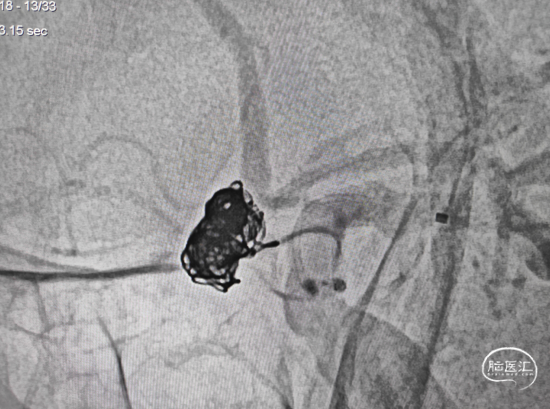

造影示瘤颈处子瘤仍显影,弹簧圈未进入子瘤,故再次用微导丝导引微导管超至子瘤口。(图示微导管头端位置)